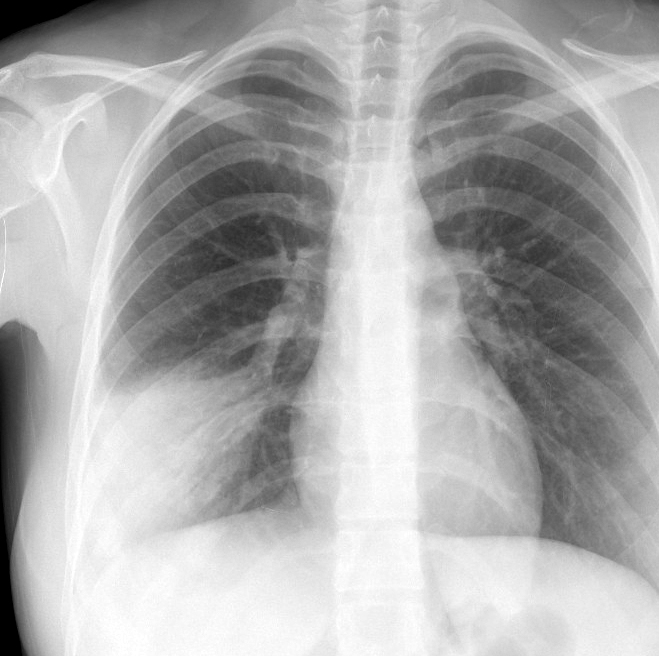

Gallery Pneumonia Case 14 RLL pneum PA

Case 14 RLL pneum PA